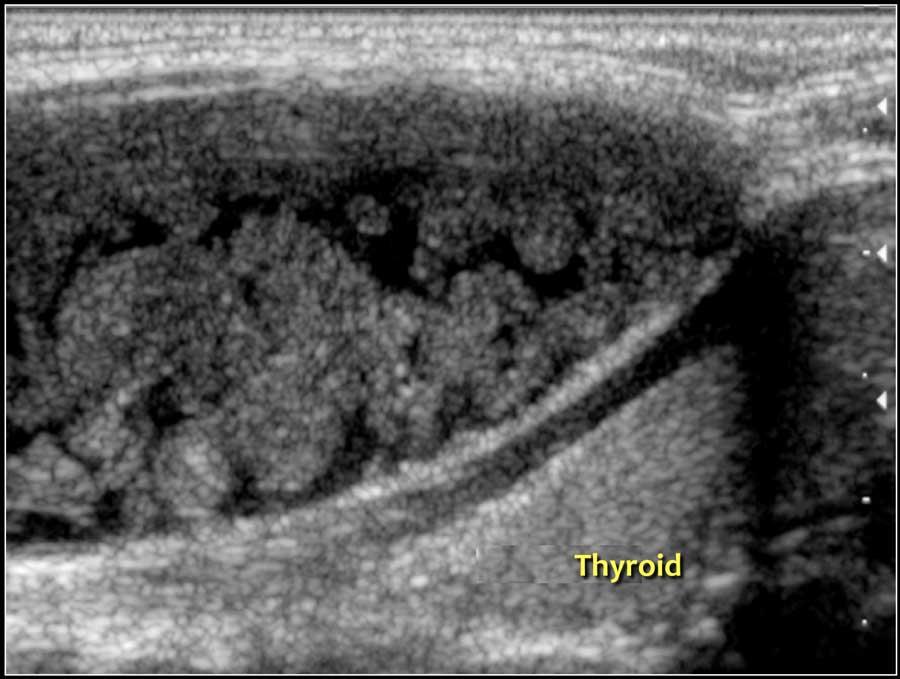

Hashimoto’s thyroiditis: An enlarged thyroid gland with a diffuse inhomogeneous structure and hyperemia is seen in a ten-year-old girl

Các dạng viêm tuyến giáp phổ biến nhất là viêm tuyến giáp Hashimoto và bệnh Graves.

Cả viêm tuyến giáp Hashimoto và bệnh Graves đều có thể biểu hiện là tuyến giáp to và tăng sinh mạch máu.

Viêm tuyến giáp Hashimoto hay viêm tuyến giáp lympho bào mạn tính là một bệnh tự miễn.

Bệnh biểu hiện với suy giáp.

Mặc dù chủ yếu là bệnh của người trung niên nhưng cũng có thể gặp ở trẻ em.

Trên siêu âm, tuyến giáp to lan tỏa và không đồng nhất.

Trên siêu âm Doppler màu, lưu lượng máu thường bình thường nhưng có thể tăng như trong bệnh Graves.

Ở giai đoạn muộn hơn, tuyến giáp teo nhỏ lại.